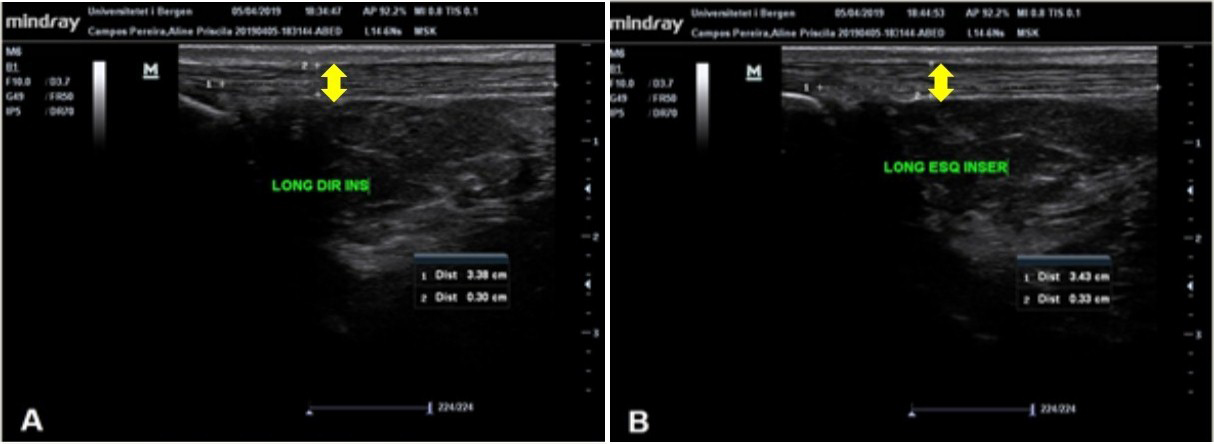

O tendão do calcâneo (TC) é o mais forte tendão do corpo humano, com grande capacidade de suportar carga. O TC é vulnerável a lesões por esforço repetitivo por receber muita carga, responsável por 18% de todas as lesões no esporte. O ultrassom (US) diagnóstico é uma técnica barata, dinâmica e rápida para avaliação de tecidos tendíneos, que pode ser associada a testes clínicos para diagnóstico de tendinopatias. Considerando que a simetria do organismo está relacionada com bom estado geral de saúde, objetivou-se neste trabalho avaliar a morfologia e aspectos clínicos do TC de indivíduos com e sem tendinopatia do TC. Participaram do estudo 28 indivíduos: 15 no grupo controle (GC) e 13 no grupo tendinopatia (GT). Os participantes passaram por avaliações específicas do TC: Exame de US, testes à palpação e clínicos. Os sujeitos do GC apresentam média de 0,407cm e 0,389cm da espessura do TC (TC direito e TC esquerdo), e não foram demonstradas anormalidades que indicassem inflamação nas imagens de US e nos testes clínicos. Nos indivíduos do GT, os valores da espessura do TC foram maiores, atingindo até 0,563cm, além de apresentarem alterações nas imagens de US para inflamação. A diferença da espessura do TC entre membros dos indivíduos do GC foi de 10%, enquanto no GT foi de 22%. Por meio dos resultados, sugere-se que diferenças da espessura do TC superiores a 20% indiquem a presença de tendinopatia, comprovadas pelos achados nas imagens de ultrassom e pelos resultados positivos dos testes à palpação e clínicos.Downloads